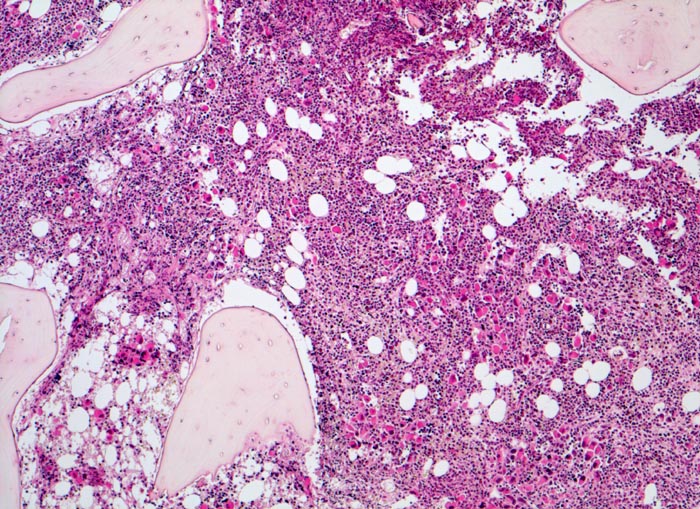

PathoPic ID 3904 - Primäre Myelofibrose (PMF)

Primäre Myelofibrose (PMF)

Knochenmark, Beckenkamm

Hyperplastisches Mark mit wechselnder Verdrängung des Fettmarks. Schon in der Übersicht sind grössere

Gruppen von Megakaryozyten erkennbar.

Splenomegalie, leichte Anämie, Leukozytose und Thrombozytose festgestellt bei einer Routineuntersuchung bei asymptomatischer Patientin.

Histologie

50